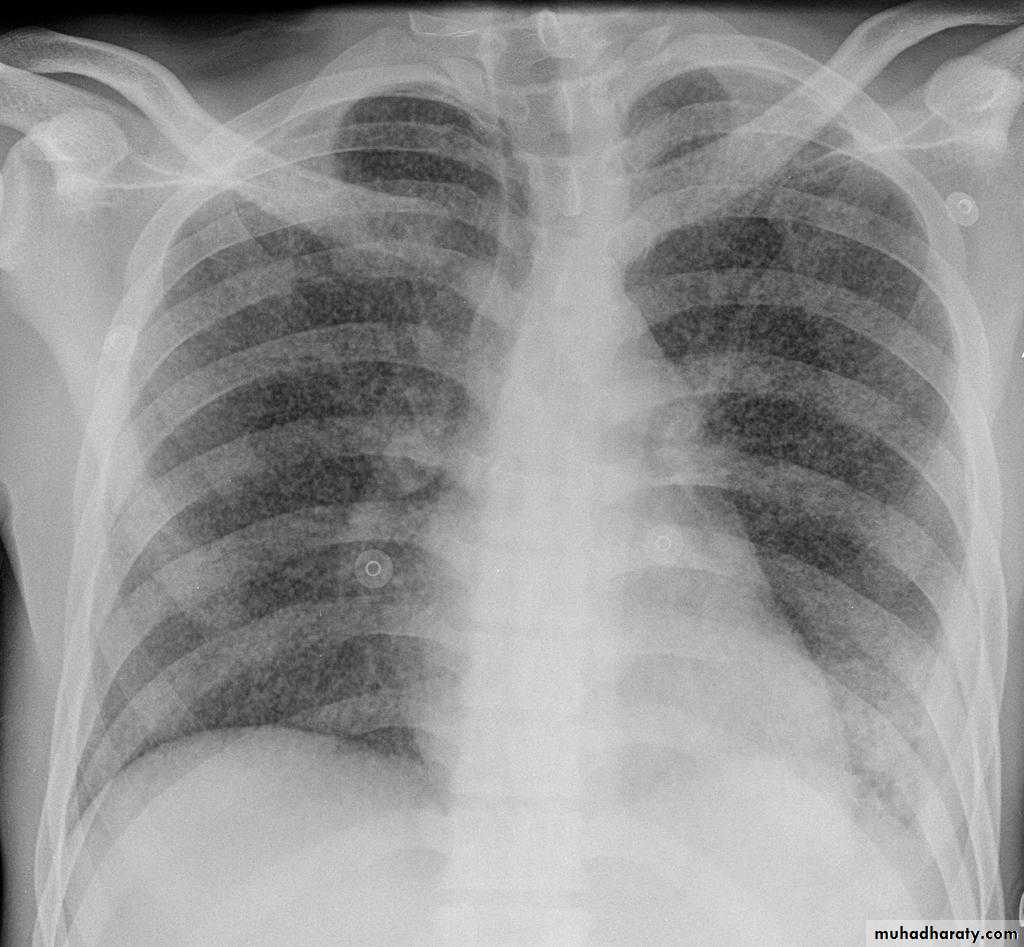

Pulmonary metastases are common and the result of metastatic spread to the lungs from a variety of tumors and can spread via blood or lymphatics.1.Cannonball metastases refer to large well circumscribed, round multiple opacities like cannonballs

2.lymphangitis carcinomatosis , is the term given to tumor spread through the lymphatics of the lung , and is most commonly seen secondary to adenocarcinoma Unfortunately up to a quarter of patients with subsequently established lymphangitic carcinomatosis have normal chest x-rays . When abnormal the most common finding is of a reticulonodular pattern, with thickening of the interlobular septae which may resemble Kerley B lines + /- pleural effusion .

3.innumerable small metastases (miliary pattern).